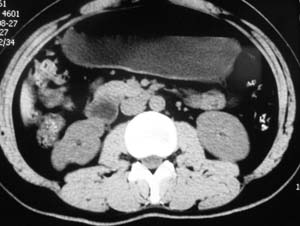

以下是引用子期在2010-3-19 20:47:00的发言:[br]血管畸形的ct增强应该有明显强化,本例并不相符合。本例双肾局部的略低密度影,累及肾盂,局部皮质明显变薄、内陷,增强扫描有轻度的强化,应考虑为炎性病变,患者为年轻男性,累及双肾的感染以结核较常见,可以没有明显的临床症状,尿中有时候也并不能查出什么;肾脓肿常有明显感染中毒症状,本例不符,另外一般的肾盂肾炎或肾小球肾炎通过小便就可确诊,其它还不能排除的是黄色肉芽肿性肾盂肾炎,然而单凭ct一般也很难鉴别。